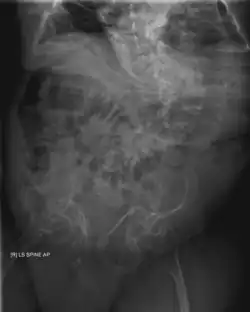

1-й тип

Коллаген нормального качества, но вырабатывается в недостаточных количествах.

- Кости легко ломаются, в особенности до пубертата

- Лёгкое искривление спины

- Слабость связочного аппарата суставов

- Пониженный мышечный тонус

- Обесцвечивание склер (глазного белка), обычно придающие им голубовато-карий цвет

- Ранняя потеря слуха у некоторых детей

- Слегка выступающие глаза

Также различают 1-й тип A и 1-й тип В по наличию или отсутствию несовершенного дентиногенеза (характеризуемый опаловыми зубами; отсутствует в IA, присутствует в IB). Помимо повышенного риска фатальных переломов костей, ожидаемая продолжительность жизни в пределах нормы.

3-й тип

Коллаген в достаточных количествах, но недостаточного качества.

- Кости ломаются легко, иногда даже при рождении,

- деформации костей, часто тяжёлые,

- возможны проблемы с дыханием,

- невысокий рост, искривление позвоночника, иногда также бочковидная грудная клетка,

- слабость связочного аппарата суставов,

- слабый мускульный тонус в руках и ногах,

- обесцвечивание склер (глазных белков),

- иногда ранняя потеря слуха.

3-й тип выделяется из других классификаций будучи типом «Прогрессивной деформации», где новорожденный представляет лёгкие симптомы при рождении и развивает вышеуказанные симптомы в процессе жизни. Продолжительность жизни может быть нормальной, хотя и с тяжёлыми физическими препятствиями.

4-й тип

Коллаген достаточного количества, но недостаточно высокого качества.

- Кости ломаются легко, особенно до пубертата

- невысокий рост, искривления позвоночника и бочковидная грудная клетка,

- деформация костей в диапазоне от слабой до средней,

- ранняя потеря слуха.

Подобно 1-му типу, 4-й тип может быть далее разделён на подклассы IVA и IVB, которым характерно отсутствие (IVA) или наличие (IVB) несовершенного дентиногенеза.